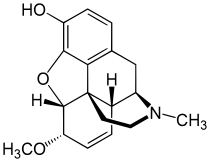

Structures of Morphine family

| Morphine family | ||||

|---|---|---|---|---|

14-Hydroxymorphine 14-Hydroxymorphine |

2,4-Dinitrophenylmorphine 2,4-Dinitrophenylmorphine |

6-Methyldihydromorphine 6-Methyldihydromorphine |

6-Methylenedihydrodesoxymorphine 6-Methylenedihydrodesoxymorphine |

6-Acetyldihydromorphine hydrochloride 6-Acetyldihydromorphine hydrochloride |

Azidomorphine Azidomorphine |

Chlornaltrexamine Chlornaltrexamine |

Chloroxymorphamine Chloroxymorphamine |

Desomorphine Desomorphine (Dihydrodesoxymorphine) |

Dihydromorphine Dihydromorphine |

Ethyldihydromorphine Ethyldihydromorphine |

Hydromorphinol Hydromorphinol |

Methyldesorphine Methyldesorphine |

N-Phenethylnormorphine N-Phenethylnormorphine |

6-nicotinoyldihydromorphine 6-nicotinoyldihydromorphine |

RAM-378 RAM-378 | ||||